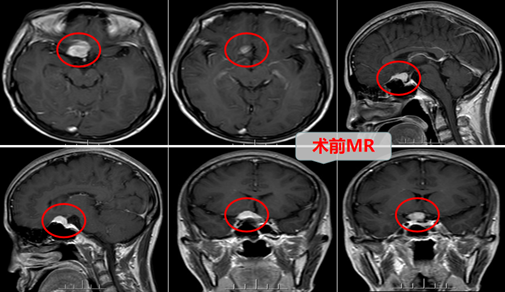

为了不耽误邱大姐的治疗,邱大姐的家属在市医院查明病情后连忙买了车票陪邱大姐一起来到广东三九脑科医院进行求医治疗。广东三九脑科医院门诊拟“鞍结节脑膜瘤”收住神经外十科。外十科团队在欧阳辉主任的带领下,非常重视,仔细地分析了病情,由于邱大姐的眼睛接近“失明”,要尽力、尽快手术挽救视力。随即外十科对邱大姐的手术进行了详细的讨论和安排:MR示“鞍结节偏右侧团块状占位性病变,呈等T1长T2异常信号影FLAIR序列呈高信号,范围约20×13×20mm,病灶轻度突入鞍内,肿瘤压迫视神经、视交叉,与邻近右侧颈内动脉关系密切”。外十科团队在结合上述信息的基础上,在征得邱大姐及其的家属的同意后,迅速为邱大姐实施了“神经内镜下扩大经鼻蝶入路,鞍结节脑膜瘤切除术+颅底重建术”。术中精准地切除肿瘤,仔细、妥善地保护视神经,并为视神经、视交叉减压,全程为微创手术,整个手术过程顺利,神经内镜显示全景视野和多角视野,为主刀医生提供多角度观察,最大限度减轻了对鼻腔内正常结构的损伤,真正做到了微创,并要使患者快速康复。